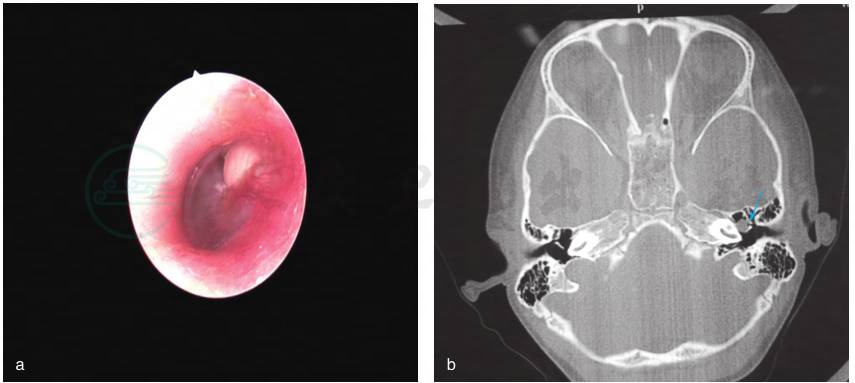

是一种于完整鼓膜内侧、有着角化鳞状上皮的不断扩张的囊状团块,出生时就存在,但通常直到婴儿或者儿童早期才被诊断出来;既往没有耳流脓、鼓膜穿孔病史和耳部手术史,但以前有中耳炎或者耳漏病史也不能完全排除先天性胆脂瘤。先天性胆脂瘤通常位于中耳的前上象限,然而,也可能位于后上象限或其他区域(图1)。

图1 先天性中耳胆脂瘤(左耳)

a.白色囊性团块物位于完整鼓膜内侧前上象限;b.颞骨CT见中鼓室腔前部团块状软组织影(箭头示)